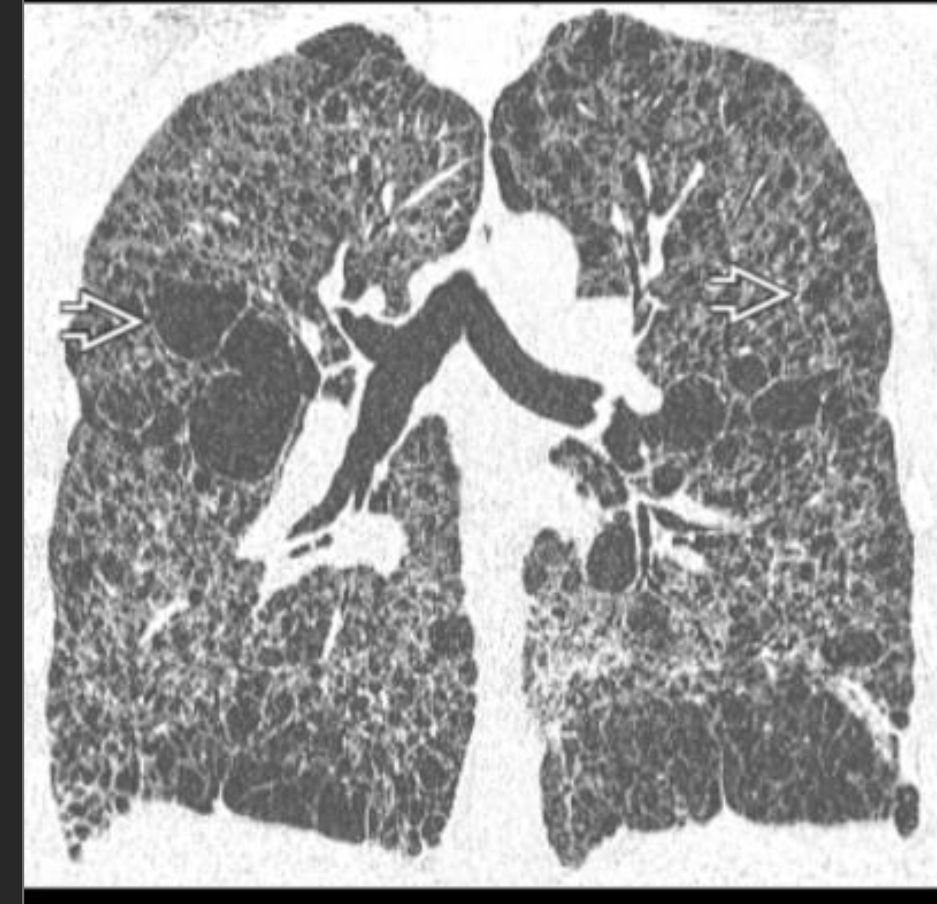

Stacked cystic spaces/honeycombing, lower lobe predominant, subpleural reticulation, architectural distortion, and volume loss

UIP Pattern–

a/w connective tissue disorders (esp RA but can be seen in others//)

IF no clinical cause, then it’s IPF